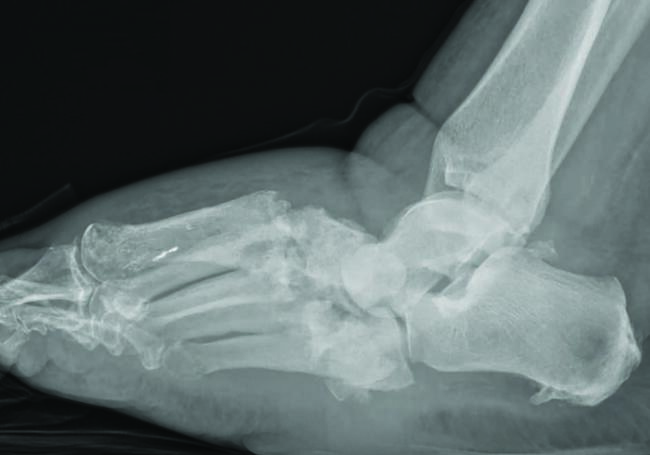

Charcot neuroarthropathy is a tissue-destructive process of the musculoskeletal system in patients with neuropathy.6-9 Most commonly affecting the foot and ankle, Charcot develops from repetitive trauma to an insensate foot. Historically, two theories describe the etiology of Charcot neuroarthropathy: the neurovascular theory; and the neurotraumatic theory. The neurovascular theory proposes that altered autonomics in patients with neuropathy leads to arteriovenous shunting and increased arterial flow, precipitating amplified osteoclastic activity and subsequent bone resorption and fracturing.10-11 The neurotraumatic theory suggests unrecognized trauma in neuropathic patients leads to repetitive injury and subsequent breakdown.12

Regardless of the cause, an acute Charcot foot is a hyperinflammatory event in the setting of immune dysregulation. Jeffcoate and colleagues hypothesized that Charcot foot developed due to the release of pro-inflammatory cytokines in an amplified immunologic response to trauma.12 They proposed a post-traumatic pathway that resulted in increased expression of TNF-α and IL-1ϐ. These cytokines induce increased expression of RANKL, which activates NF-κϐ (a transcription factor), mobilizing osteoclasts for osteolysis. Such a process would be a healthy response to injury, but in the setting of neuropathy, the injured site may sustain repetitive insults. Perhaps these repetitive insults manifest immune dysregulation, leading to an uncontrolled hyperinflammatory state.12-13 There is limited research to support this elegant theory, but there is acceptance of the proposed pathway as the most likely mechanism driving Charcot collapse.

Uccioli and team found that the patient with acute Charcot exhibits an inflammatory monocyte phenotype compared to healthy controls with diabetes.8 They also found increased concentrations of circulating cytokines in patients with acute Charcot.14 Baumhauer and coworkers utilized immunohistochemistry methods to evaluate cytokine mediators of bone resorption in osseous specimens of patients with Charcot arthropathy.15 They found enhanced activity of osteoclasts in the setting of IL-1, IL-5, and TNF-α activity,15 which supports the pro-inflammatory hypothesis.12-15

Management of the acute Charcot foot involves management of any present ulceration or infection and aggressive offloading through immobilization to prevent progression of deformity and amplification of the inflammatory cycle.16-17 There is some early evidence to suggest using immunomodulators such as TNF-ɑ inhibitors in the management of acute Charcot foot.18 Bisphosphonates are occasionally part of the treatment for the acute Charcot foot with mixed results.19 Surgical management of the acute Charcot foot is rarely indicated as surgical trauma may worsen the inflammatory cascade, resulting in even more bone resorption.